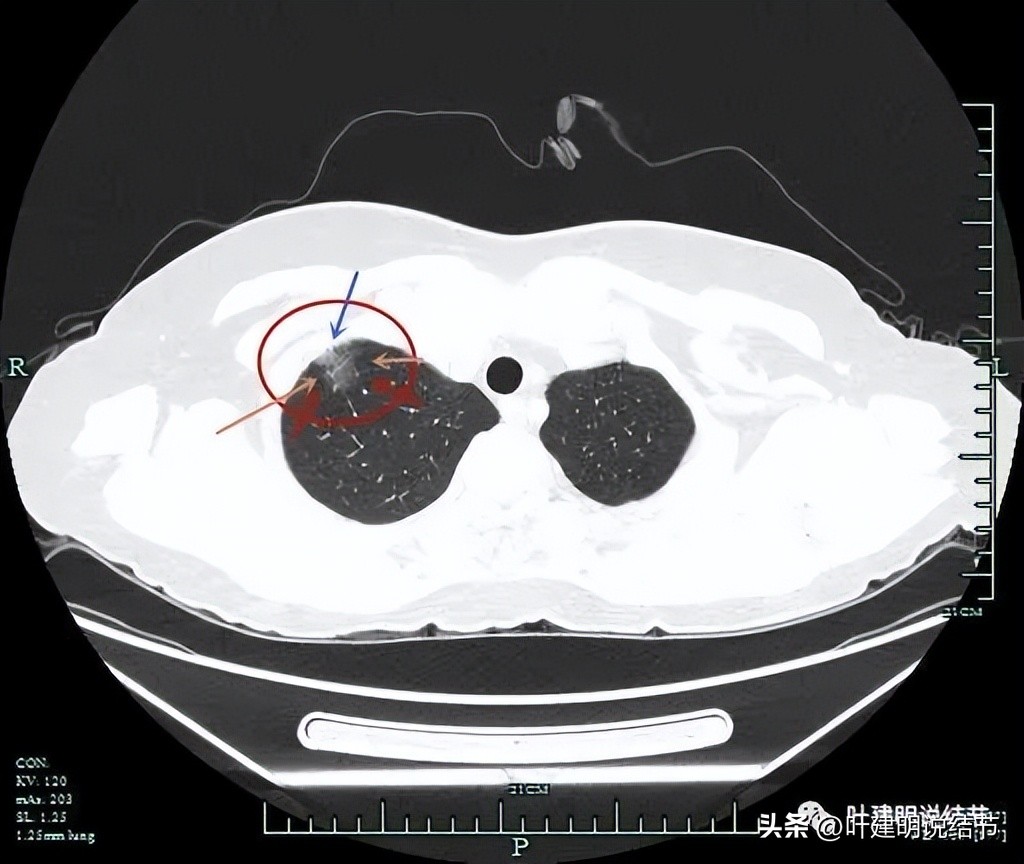

胸膜间的间隙不清,病灶表面不平,轮廓清

毛刺明显,表面不平,轮廓清楚

分叶征明显,毛刺征也明显

靶扫描上图层面见病灶内部有实性成分,与胸壁间没有间隙(蓝色箭头),灶内有血管穿行(桔色箭头),整体轮廓清(红色箭头)。

实性部分密度不均,散在,杂乱(粉色箭头),有明显血管发出分支进入病灶(桔色箭头)。

灶内血管穿行、边缘不平有毛刺、整体轮廓清。